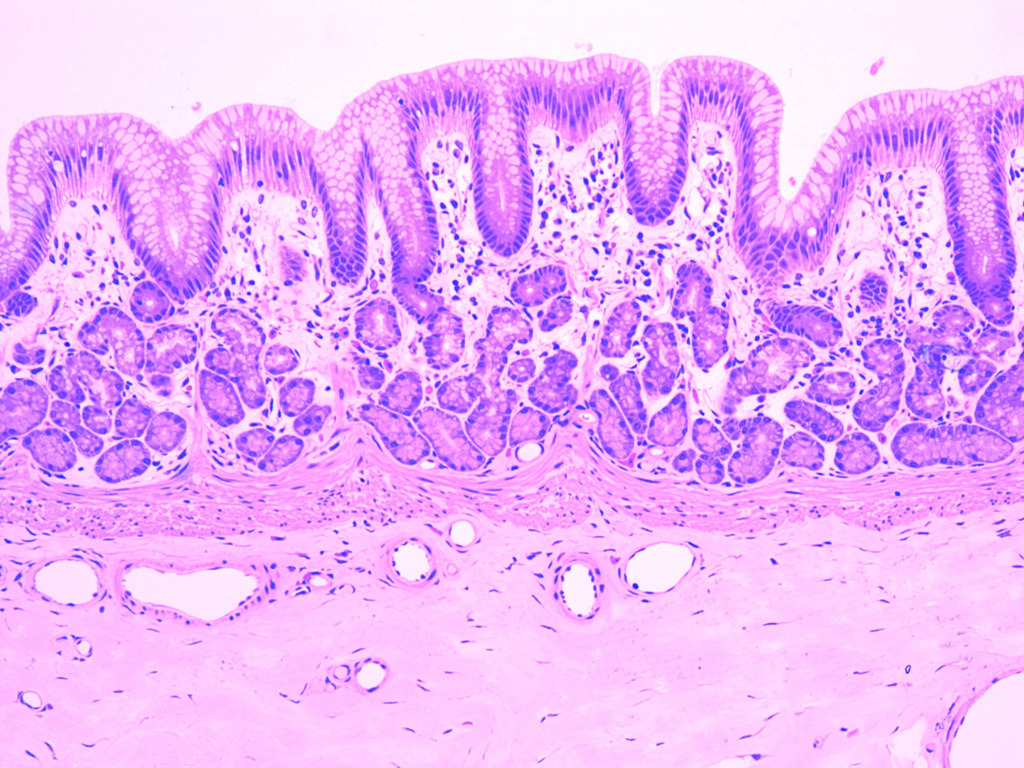

- Особенности строения слизистой оболочки тонкой кишки: ворсинки, крипты, эпителий, его клеточный состав. Различия в строении двенадцатиперстной, тощей, подвздошной кишки. Морфологическая характеристика толстой кишки, клеточный состав эпителия крипт. Лимфоидная ткань тонкой и толстой кишки.